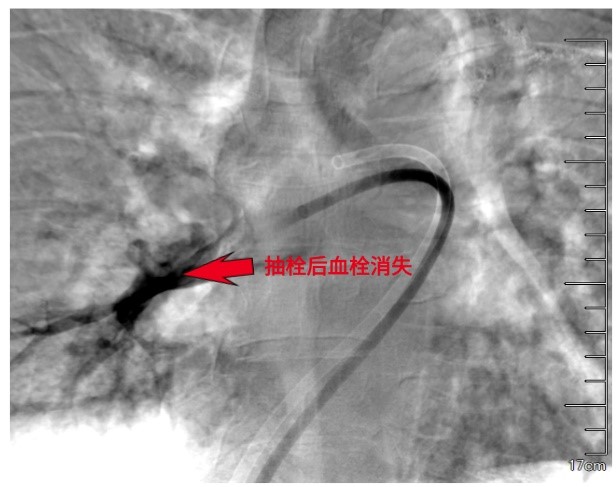

手术在现代化的杂交介入手术室进行。患者清醒地平卧在手术台上,医生在其腹股沟区消毒、局麻后,穿刺股静脉,送入一根比圆珠笔芯还细的导管。在X线透视的“实时地图”导航下,导管轻柔地经过心脏,直抵被血栓“堵死”的肺动脉主干。

医生将一种专用的大腔血栓抽吸导管沿导丝送至血栓内部。随着负压的启动,血栓被源源不断地吸入体外收集装置。术后即刻的肺动脉造影显示,先前中断的血流通道被重新打通,右心压力随之下降。这场在血管内部进行的“疏通作业”,安静而高效,没有开胸的惊心动魄,却完成了同样关键的使命。